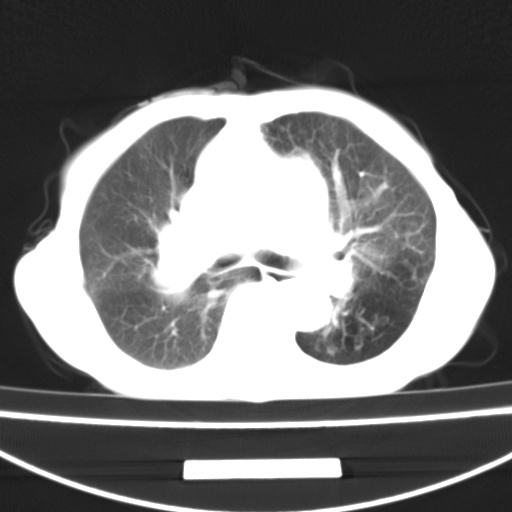

患者 女 67岁,反复咳嗽咳痰2年,加重伴喘及双下肢浮肿1月

陈旧性肺结核、慢性支气管炎、支气管扩张症、肺心症、肺动脉高压。

诸大血管及f肺门血管增粗迂曲.左下肺多发薄壁空腔影.部分非也透亮度增高.薄曾扫描可区分肺气肿类型.考虑1.慢性支气管炎 2.左下肺支气管扩张 3.肺气肿 4 肺动脉高压5.是否有先心病病史

考虑1.慢性支气管炎 2.左下肺支气管扩张 3.肺气肿 4 肺动脉高压

慢支炎、肺气肿、双肺感染、左下囊状支扩。

慢支、肺气肿、肺动脉高压;左下肺囊状支扩并粘液栓形成。